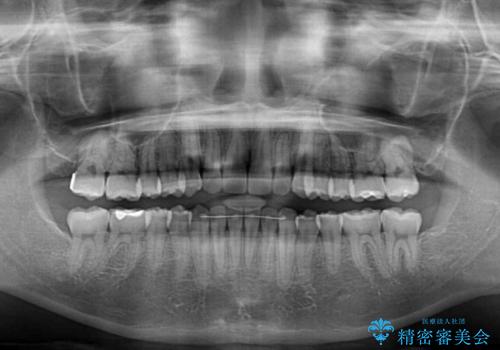

前歯のクロスバイトをインビザライン矯正で改善

- 前歯のデコボコと上下のクロスバイトを気にして来院された患者様です。

インビザラインを用い、IPR(歯と歯の間を削る)と歯列全体を拡大させることで、歯並びを整えていくこととしました。

上の前歯が下の前歯を乗り越える際、奥歯がほとんど咬めない時期があり、乗り越えた後も、インビザライン特有の奥歯の咬みにくさが続きました。

咬み合わせ改善のために治療期間を要しましたが、最終的に奥歯はしっかりと咬めるようになりました。